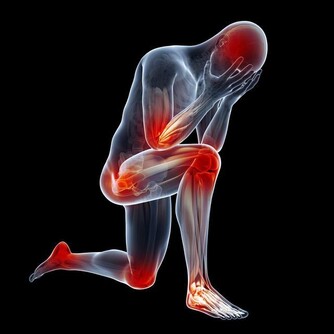

住在中國浙江的一對夫妻,因為工作繁忙的關係而沒時間陪伴10歲的女兒。於是他們買了一隻手機給女兒在無聊時可以打發時間。但有天女兒玩手機玩到一半,聽到媽媽呼喚而抬頭,卻聽到「喀擦」一聲,而且無法動彈,經過醫生的診斷為「頸椎錯位」。

醫生表示,小女孩的頸椎第一、二、三椎向前錯位,「我從醫30多年,第一次碰到這麼嚴重的頸椎病發生在這麼小的孩子身上!」

醫生提醒,人的頸椎就像彈簧一樣,如果常常低著頭,保持同一個姿勢,很容易出現彈性疲乏,而且無法復原,不論大人或小孩,如果經常有,頭暈,頭痛,注意力不集中,甚至噁心想吐著症狀,就有可能是頸椎病變的前兆!